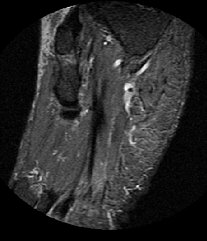

kernspinnereien

3. ... man(n) gab mir ne CD mit den Bildern mit.

2. ... diese CD hab ich natürlich mal in den PC eingelegt ... und mir ein Bild angeschaut ... mehr brauch ich nicht, denn die Diagnose ist:

Ich leide an Höhlenmalereien !! *gg*